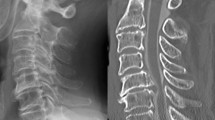

Imaging factors Imaging factors including types of OPLL (continuous, segmental, mixed and localized types Fig.Ā 1A)27, canal narrowing rate (thickness of OPLL at its peak level / antero-posterior diameter of corresponding spinal level (%) in lateral radiogram of cervical spine (Fig.Ā 1B), post-operative change of C2-7 angle (C2-7 angle was measured as angle between inferior endplates of C2 and C7 vertebral bodies (Fig.Ā 1C), and post-operative change of C2-7 angle was calculated as subtraction of postoperative C2-7 angle from preoperative C2-7 angle), change of C2-7 range of motion (ROM was calculated as subtraction of C2-7 angle from extension position to flexion position (Fig.Ā 1D), and change of C2-7 range of motion was calculated as (preoperative C2-7 ROM)ā(postoperative C2-7 ROM)). Spinal cord signal intensity change in magnetic resonance imaging (MRI) T2 weighted image were assessed because the intramedullary signal change had been reported as one of the imaging factors for prediction of surgical outcome (Fig.Ā 1E)28.

Methods for imaging analyses. (A) OPLL was classified into 4 types (continuous, segmental, mixed and localized types). (B) Canal narrowing rate was calculated as followings, thickness of OPLL at peak (b)/antero-posterior diameter (a), in lateral radiogram of cervical spine in neutral position. (C) C2-7 angle was measured as angle between inferior endplates of C2 and C7 vertebral bodies (C). Lordosis curve was expressed as positive value and kyphosis curve was expressed as negative value. Post-operative change of C2-7 angle was calculated as subtraction of postoperative C2-7 angle from preoperative C2-7 angle. (D) C2-7 range of motion (ROM) was calculated as subtraction of C2-7 angle from extension position to flexion position (D), and change of C2-7 range of motion was calculated as (preoperative C2-7 ROM)ā(postoperative C2-7 ROM)). (D) Spinal cord signal intensity change in magnetic resonance imaging (MRI) T2 weighted image were assessed because the intramedullary signal change had been reported as one of the imaging factors for prediction of surgical outcome (E, arrow).